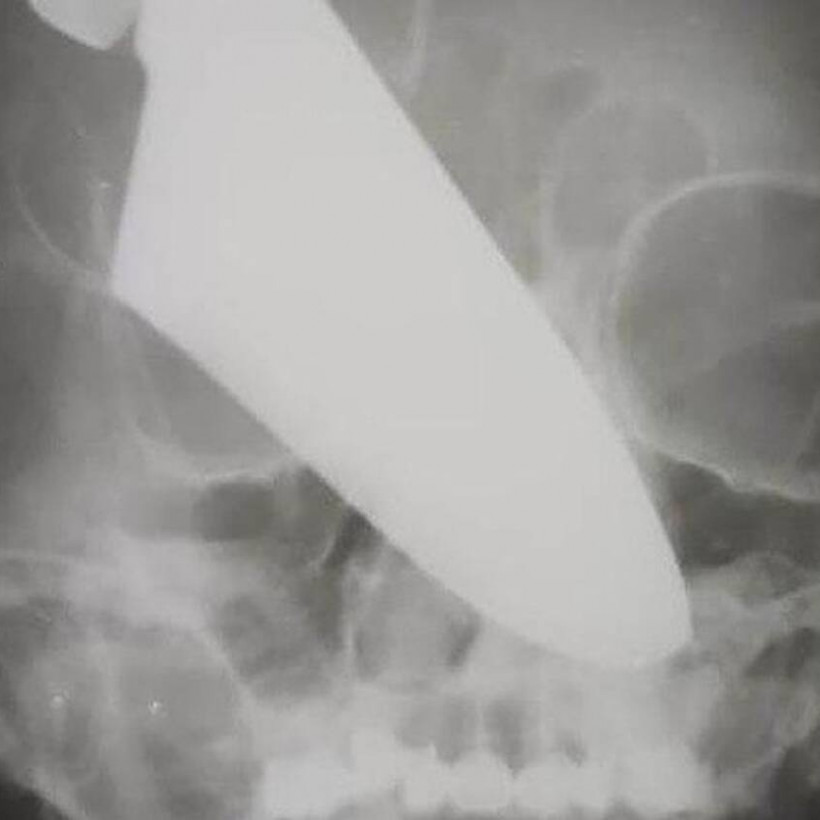

Μπροστά σε ένα απίστευτο περιστατικό βρέθηκαν γιατροί σε νοσοκομείο του Κράσνονταρ της Ρωσίας, όταν μια γυναίκα βρέθηκε στα επείγοντα με ένα μαχαίρι καρφωμένο στη μύτη της!

Η γυναίκα, το όνομα της οποίας δεν δόθηκε στη δημοσιότητα, είχε στη μύτη της ένα μαχαίρι 25 εκατοστών μετά από επίθεση που δέχτηκε στο δρόμο από ληστή, ο οποίος συνελήφθη λίγο αργότερα.

Μετά από μια επέμβαση που κράτησε πάνω από τέσσερις ώρες, το μαχαίρι αφαιρέθηκε και δεν άφησε κάποιο πρόβλημα στην 60χρονη.